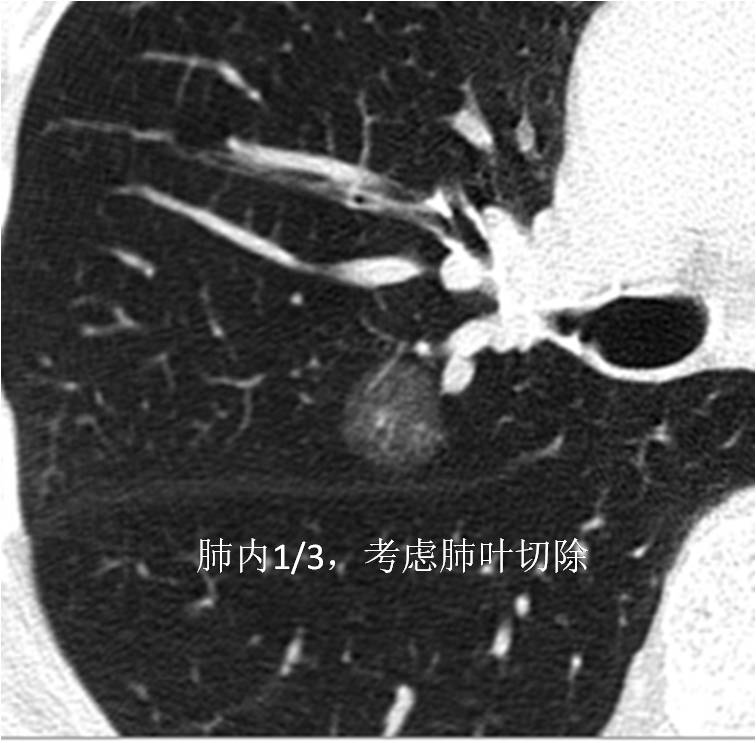

1. 肺组织按照从内到外大约分为内1/3,中1/3和外1/3三个区域。病灶位于肺组织1/3区域内,可以考虑行肺楔形切除术。病灶位于肺组织内1/3和中1/3区域内,可以考虑行肺段切除术或肺叶切除术。